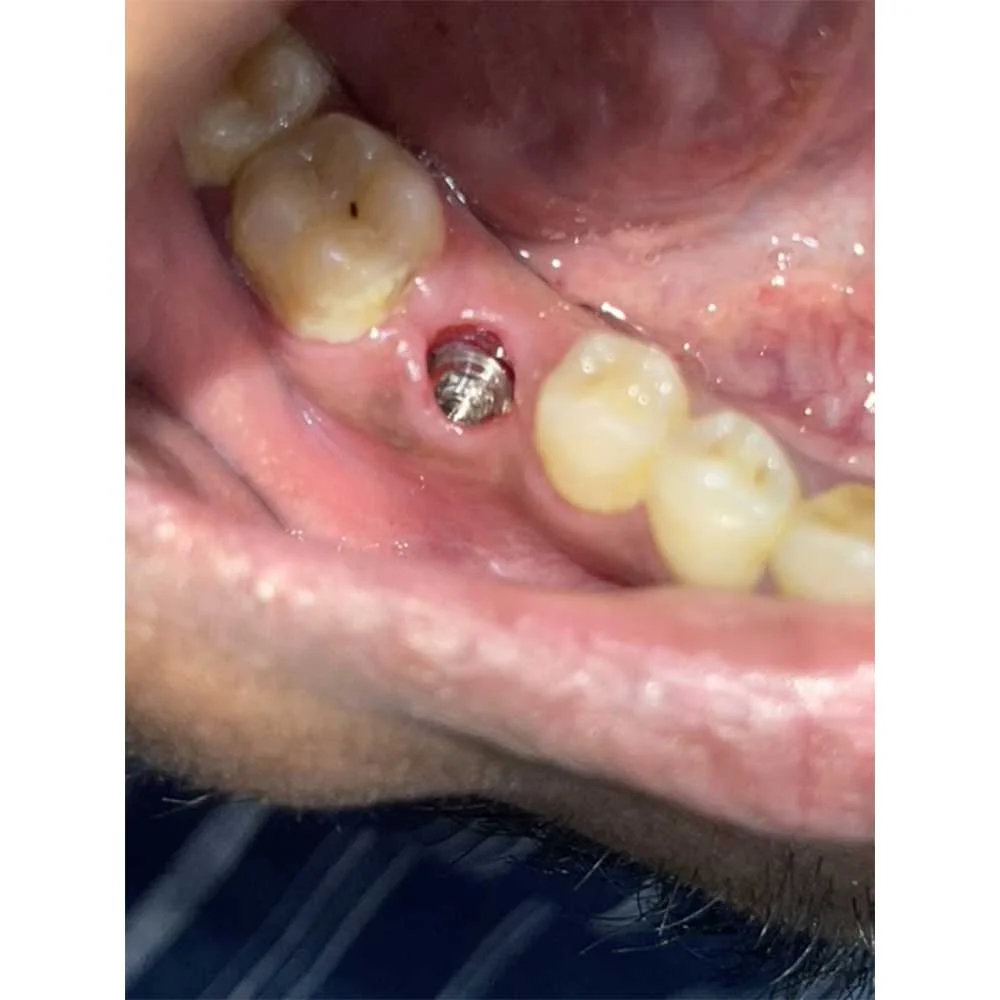

1. Single Tooth Implants:Ideal when it comes to replacing a single lost tooth without affecting the neighbouring teeth.

Full Mouth Implants

Dental Implants